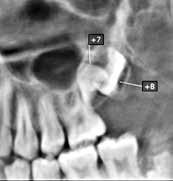

DE FLESTE PATIENTER, der får udført ortodontisk kirurgi, får fjernet deres visdomstænder inden den egentlige behandling. De CBCT-undersøgelser, der optages i forbindelse med ortodontisk kirurgi, har imidlertid et større billedfelt (FOV) og dermed en lavere billedopløsning end de optagelser, der normalt tages før fjernelse af visdomstænder. Forskere fra Aarhus Universitet (Institut for Odontologi og Oral Sundhed) og Sydvestjysk Sygehus, Esbjerg (Kæbekirurgisk Afdeling), har derfor undersøgt, hvor godt forskellige fund på CBCT med stort billedfelt korrelerer med de kliniske fund, der kan registreres i forbindelse med operationen. 209 tredjemolarer fra underkæben blev i perioden 20152017 fjernet på 134 patienter, der var skrevet op til ortodontisk kirurgi. Tre uafhængige eksperter registrerede på CBCT med stort billedfelt tændernes lejring, rodantal og rodmorfologi samt en række parametre, som vedrørte tændernes relation til canalis mandibulae. I forbindelse med operationerne blev de samme tandrelaterede forhold registreret, og i relation til canalis mandibulae blev det registreret, om nerven var synlig efter fjernelse af tanden, om der var furer i roden efter nerven, og/eller om patienten ved suturfjernelsen havde føleforstyrrelser svarende til n. alveolaris inferior.

Generelt var der god korrelation mellem de radiologiske og kliniske fund, når det drejede sig om tændernes lejring, rodantal og -morfologi. Derimod var der meget lave positive prædiktive værdier, når det drejede sig om tændernes relation til canalis mandibulae. Med andre ord kunne man ikke ud fra optagelserne forudsige, om patienterne havde en større risiko for føleforstyrrelser efter behandlingen.

På den baggrund finder forfatterne, at CBCT-fund, der har relation til canalis mandibulae, ikke bør indgå i den information, man giver til patienterne inden operationen.

Matzen LH, Schropp L, Hermann L, Ingerslev J, Wenzel A. Reliability of radiographic findings in large FOV CBCTs of mandibular third molars as basis for pre-operative patient information. Acta Odont Scand 2022;80:210-7.tandlægen.dk har fokus på livslang læring for alle vores faggrupper - for løbende at styrke vores faglige viden og kunnen til gavn for patienterne.